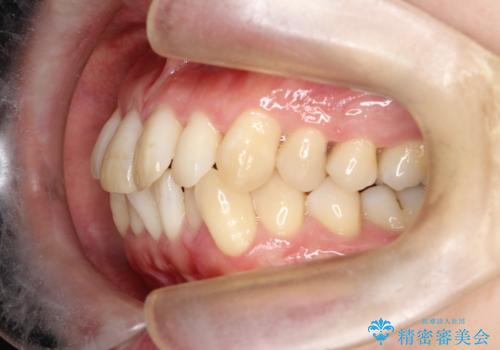

- 前歯の凸凹と前突感を改善するため、上下左右の4番を抜歯し、空いたスペースを利用して前歯を後方へ下げる審美ワイヤー矯正を計画しました。抜歯後は透明で目立ちにくい審美ブラケットを装着し、ワイヤーを用いて徐々に歯列を整えます。毎月1回の調整を通じて歯並びの変化を確認しながら、丁寧に矯正を進め、約2年で理想的な歯列と噛み合わせを完成させることを目指します。

前歯が前に出ていることや歯並びの凸凹が気になるという主訴でした。十分なスペースを確保するため上下左右の第一小臼歯(4番)を抜歯し、そこに前歯を移動させて整列を行いました。矯正装置には目立ちにくい透明なブラケットを選択し、見た目のストレスを軽減。矯正期間中は定期的な通院でワイヤーを微調整し、無理なく確実に歯を動かしました。治療後は前歯が自然な位置に下がり、口元の突出感が解消されるとともに、美しく整った口元に仕上がり、患者様にも大変喜んでいただけました。